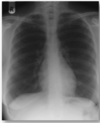

On the image shown is this xray taken on inspiration or expiration?

How can you tell?

what midline structures can you see?

What structures can be seen entering the lung?

The Xray is taken during inspiration as there is a flattened costodiaphragmatic recess, the lung fields are large and you can clearly see ribs 5-7 anteriorly (the curved ribs) and to rib 10 posteriorly.

Centrally you can see the arch of the aorta (superior)

Inferior to this you can see the pulmonary trunk

On each lung the hilum is shown and the branching vessels entering the lung